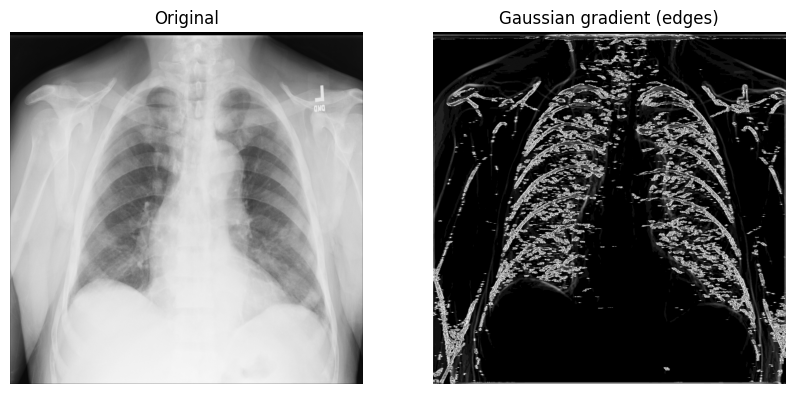

高斯梯度幅值方法¶

另一种有用的边缘检测方法是高斯(梯度)滤波器。它通过高斯导数计算多维梯度幅值,并有助于去除高频图像分量。

1. 使用sigma(标准差)参数(您将在下面的示例中使用2)调用scipy.ndimage.gaussian_gradient_magnitude()

x_ray_image_gaussian_gradient = ndimage.gaussian_gradient_magnitude(xray_image, sigma=2)2. 显示原始X光片和应用了高斯梯度滤波器的X光片

fig, axes = plt.subplots(nrows=1, ncols=2, figsize=(10, 10))

axes[0].set_title("Original")

axes[0].imshow(xray_image, cmap="gray")

axes[1].set_title("Gaussian gradient (edges)")

axes[1].imshow(x_ray_image_gaussian_gradient, cmap="gray")

for i in axes:

i.axis("off")

plt.show()